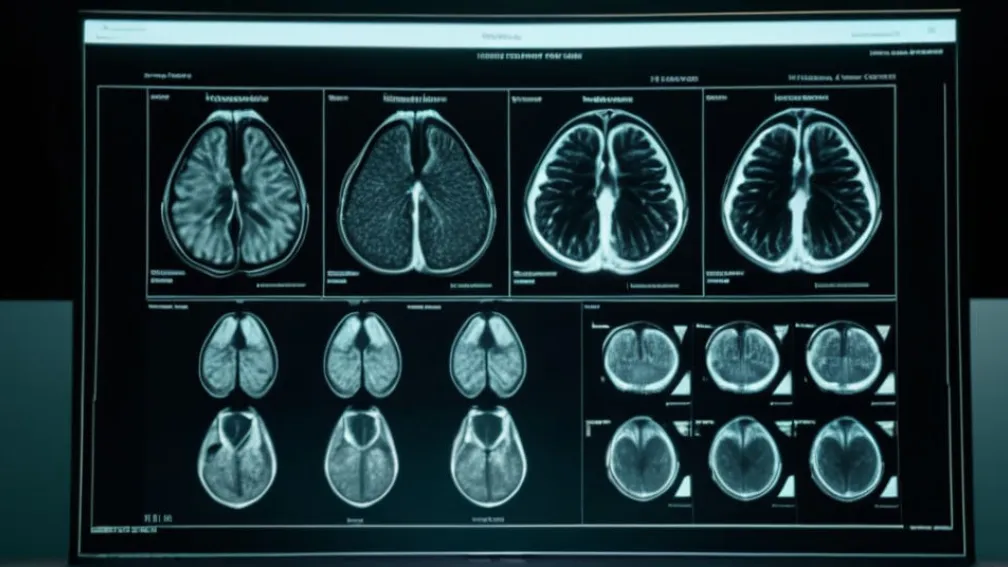

Medicul personal al lui Donald Trump a dat publicității rezultatele RMN-ului său, disipând speculațiile și afirmând că fostul președinte se află într-o "excelentă" stare de sănătate generală.

După săptămâni de speculații intense privind starea de sănătate a fostului președinte american Donald Trump, medicul său personal, Dr. Sean Barbabella, a făcut publice rezultatele unei scanări RMN efectuate în luna octombrie.

Purtătoarea de cuvânt a Casei Albe, Karoline Leavitt, a citit un memoriu oficial în care se detaliază că RMN-ul abdominal al lui Trump a arătat "fără anomalii". Documentul subliniază că "toate organele majore par foarte sănătoase și bine irigate cu sânge".

"Toate funcțiile examinate sunt în limite normale, fără afecțiuni acute sau cronice. În concluzie, această examinare detaliată respectă standardul pentru un control de sănătate executiv pentru vârsta președintelui Trump și confirmă că acesta continuă să fie într-o stare generală excelentă", a declarat Leavitt.

Memoriul reiterează, de asemenea, că "sistemul său cardiovascular" a fost evaluat ca fiind "excelent". Anterior, starea de sănătate a lui Trump a fost subiectul multor discuții, în special din cauza umflăturilor la glezne și a petelor misterioase de pe mână. În luna iulie, Casa Albă a raportat că președintele suferea de "insuficiență venoasă cronică".

Într-un comentariu separat, Donald Trump a descris propriile rezultate RMN ca fiind "perfecte". Pe un zbor cu Air Force One, el a declarat reporterilor că nu știe exact ce parte a corpului său a fost scanată, dar a menționat că nu a fost creierul, deoarece a trecut cu brio un test cognitiv.